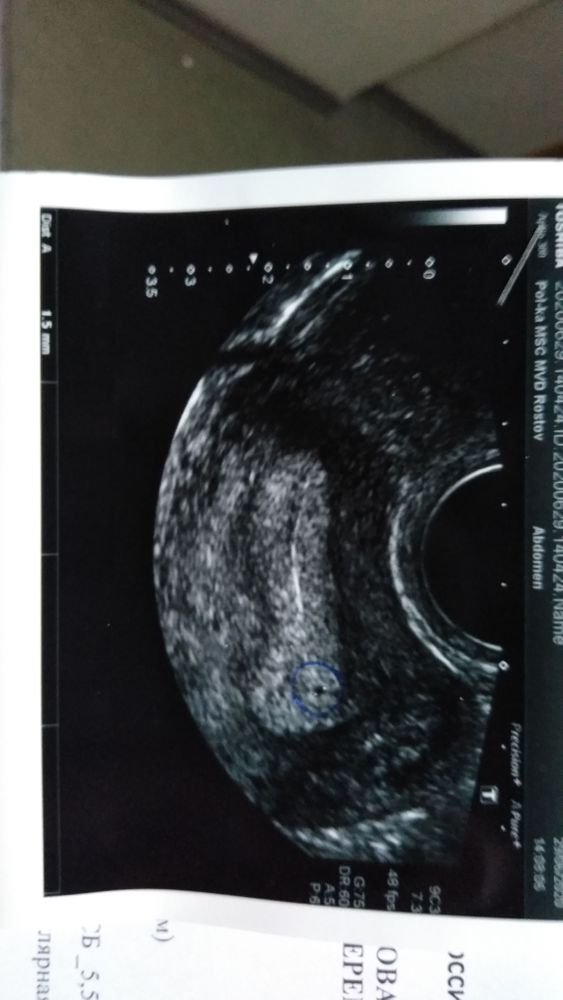

Первый триместр беременностиВсем привет, мне 34 года, ходила к гинекологу всю весну, всё подлечила, муж тоже всех обошел, начали планировать. 25 мая первый день последних месячных - от него врачи считают акушерские недели. Овуляция была 9 и 10 июня, ПА 9 июня, 22 июня пошли - думала, в этом уже ничего не будет, но на утро они закончились, делала несколько тестов каждый день - все положительные и полоска всё ярче))) 28 июня хгч показал всего 168, узи 29 июня показал плодное яйцо 1.5 мм и два желточных мешочка и все, больше ничего не видно. 2 июня хгч подрос до 632. Врач одна говорит низкий хгч срочно в госпиталь, вторая, что надо хгч еще через 3 дня и узи 13 июля. Уже не знаю, что и думать. Все это время уже 12 дней мазня коричневая, вчера вообще с прожилками мелкими была.